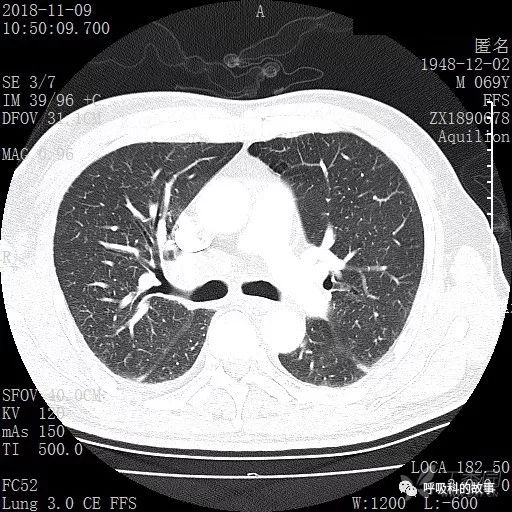

胸部增强CT示右肺门占位伴远端阻塞性肺炎,纵膈、右肺门、右侧颈根部、右侧腋下及肝门部肿大淋巴结。两侧胸腔少量积液。

肺窗CT